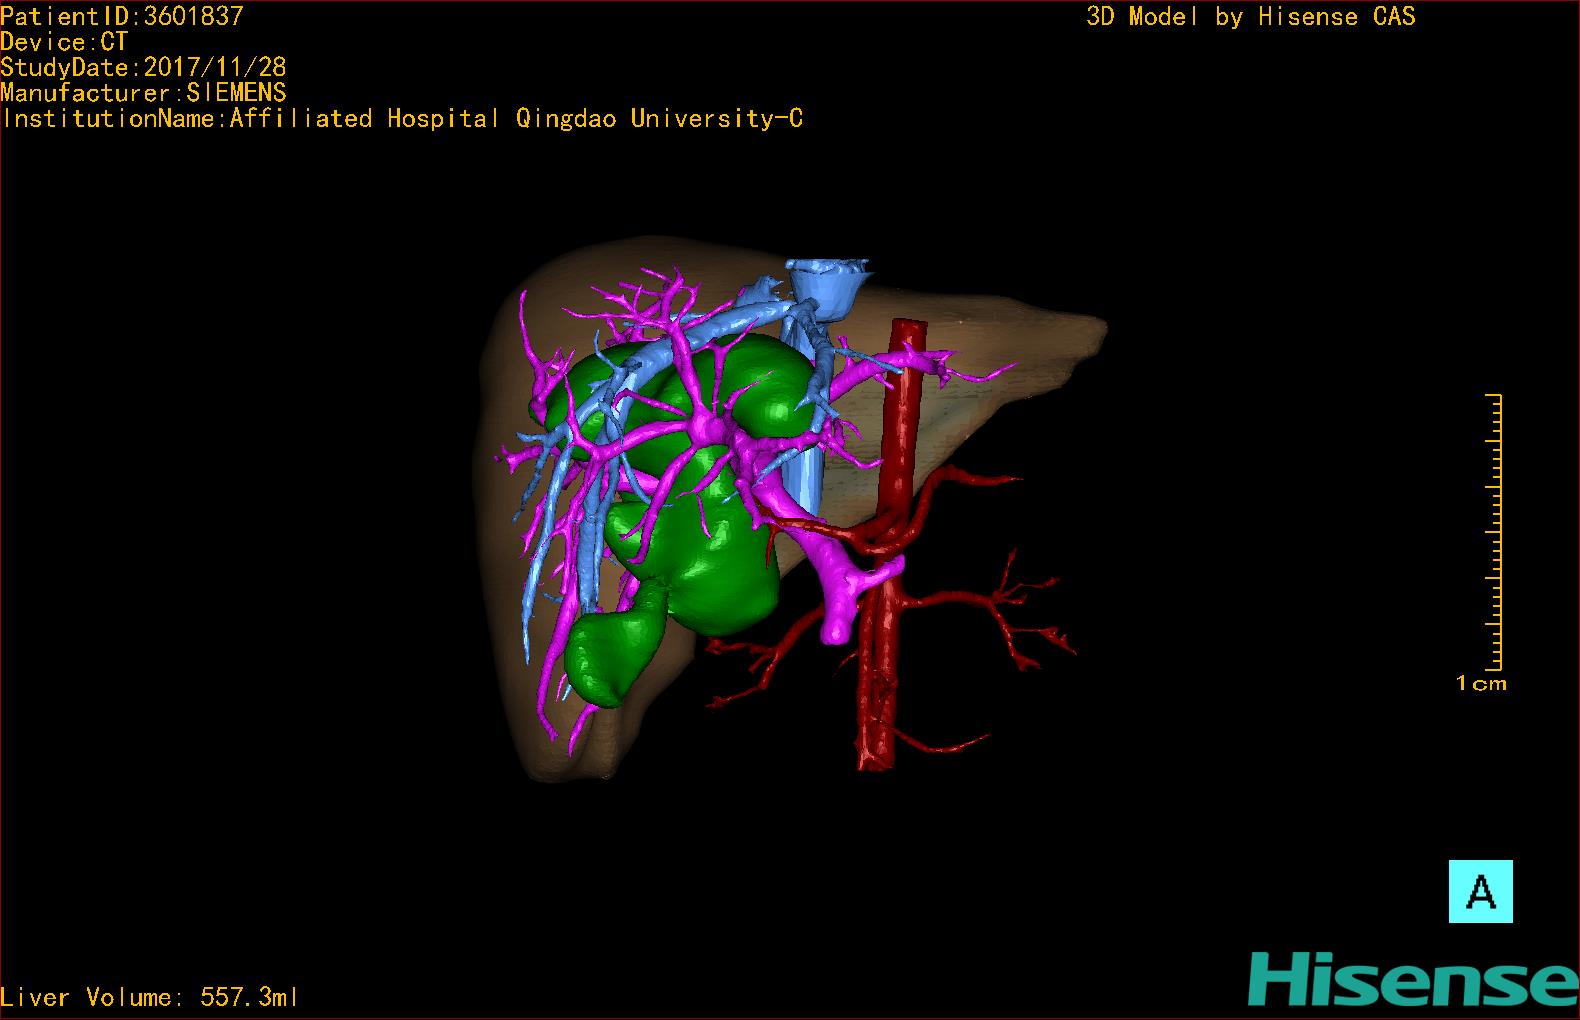

10、三维重建虚拟肝脏、胆道显像技术

三维虚拟肝脏技术是在二维影像学资料如CT等图像的基础上,通过三维重组软件和工具,比如青岛大学附属医院与海信医疗集团联合自主研发的海信计算机辅助手术系统(Hisense Computer Assisted Surgery,Hisense CAS),目前已投入临床并指导实际应用,利用该类系统对二维影像学的数据资料进行三维立体分析,重组形成立体的、有空间结构的、虚拟的肝脏三维图像。这项技术较传统的二维平面成像技术,有着明显的优势,3D虚拟肝脏技术可以构造出一个虚拟的、可视化的肝脏模型。通过对这种模型的观察,可以很容易地分辨出肝脏器官的组织结构、解剖特点,直观研究肝外胆总管的形态差异,明确肝内胆管的形态、走形、是否合并扩张、狭窄及结石,胰胆管合流的形态及共同通道内是否有狭窄、扩张和结石等病变情况,预先规划处理可能合并存在的肝内胆管扩张、狭窄或其他复杂胆道畸形,清晰地显示肝内脉管系统,包括门静脉、肝动脉及肝静脉的走行、分支,并可多角度、全方位观察病变胆道与其周围重要血管尤其是伴行的门静脉之间的解剖关系,大大提高了外科医师在术前对肝脏内部各管道结构及其变异判断的精确性和可靠性,精准地对病变进行判断和评估,还可根据患者自身的病变特点,制定出合理、个体化的手术方案,最大限度地降低术中和术后并发症发生率,并术中导航实时指导手术,提高手术的精准性和成功率。

图10:先天性胆管扩张症囊肿型三维重建虚拟肝脏、胆道显像

a 图为术前二维CT扫描图像,箭头所示为肝内胆管扩张;b 图为CT经多平面重组技术(MPR)图像后处理所得的重建图像,可显示胆总管明显扩张合并肝内胆管扩张;c 图为MRCP显示胆总管呈囊柱状扩张,直径>1 0 cm,伴肝内胆管扩张;d 图示Hisense CAS三维重建清晰显示肝脏、胆道系统及其与门静脉、肝动脉、肝静脉等之间的空间解剖关系;e 图示Hisense CAS可从任意角度以不同脏器组合显示,明确胆道系统与其伴行的门静脉系统的空间解剖关系;f 图示胆道系统立体形态及与肝脏整体的空间关系,箭头处显示肝内胆管狭窄部位发生于左右肝管汇入肝总管处。术前规划需行肝内胆管扩大成形术。

图11:先天性胆管扩张症梭状型三维重建虚拟肝脏、胆道显像

a 图为术前二维CT扫描图像,箭头指示肝内胆管扩张;b 图为CT经多平面重组技术(MPR)所得的重建图像,可粗略地判断病变胆管的位置;c 图示术前Hisense CAS三维重建清晰显示胆管的病理形态及其与肝内三套血管系统的解剖关系;d 图示胆道系统与其伴行的门静脉系统的空间解剖关系;e 图为胆道系统立体形态,箭头处指示迷走胆管,源自肝脏直接汇入胆总管。术前规划先将迷走胆管与肝总管吻合成形,再行肝总管空肠Roux-en-Y吻合术。

图12:先天性胆管扩张症梭状型合并左右肝管分别汇入胆总管囊肿三维重建虚拟肝脏、胆道显像

a 图为术前二维CT图像;b 图为CT经多平面重组技术(MPR)所得的三维重建图像,可粗略地判断病变胆管的位置;c 图为MRCP显示胆总管梭状扩张;d 图为术前Hisense CAS三维重建显示胆管的分布走形及其与肝内三套血管系统的解剖关系;e 图为胆道系统立体形态及与肝脏整体的空间关系,箭头处显示对于左右肝管分别汇入胆总管囊肿中,整个肝总管也明显扩张而成为囊肿的一部分。术前规划为先将囊肿完全切除,左右肝管合并成形后再与空肠吻合。